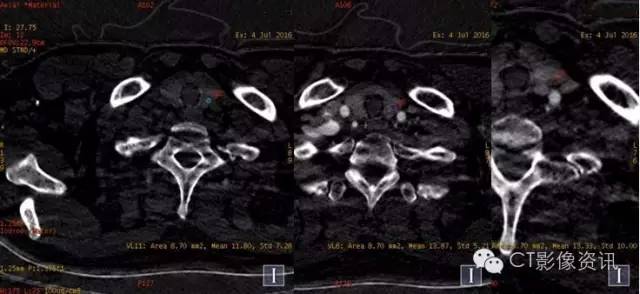

能谱曲线

右肺、上腔静脉及纵隔淋巴结病灶曲线斜率基本一致,而左甲状腺病灶能谱曲线与其明显不一致,综合CT平扫及强化各期特点以及病理结果,上腔静脉病灶考虑癌栓;左甲状腺病灶考虑甲状腺腺瘤(非转移病灶)可能大。